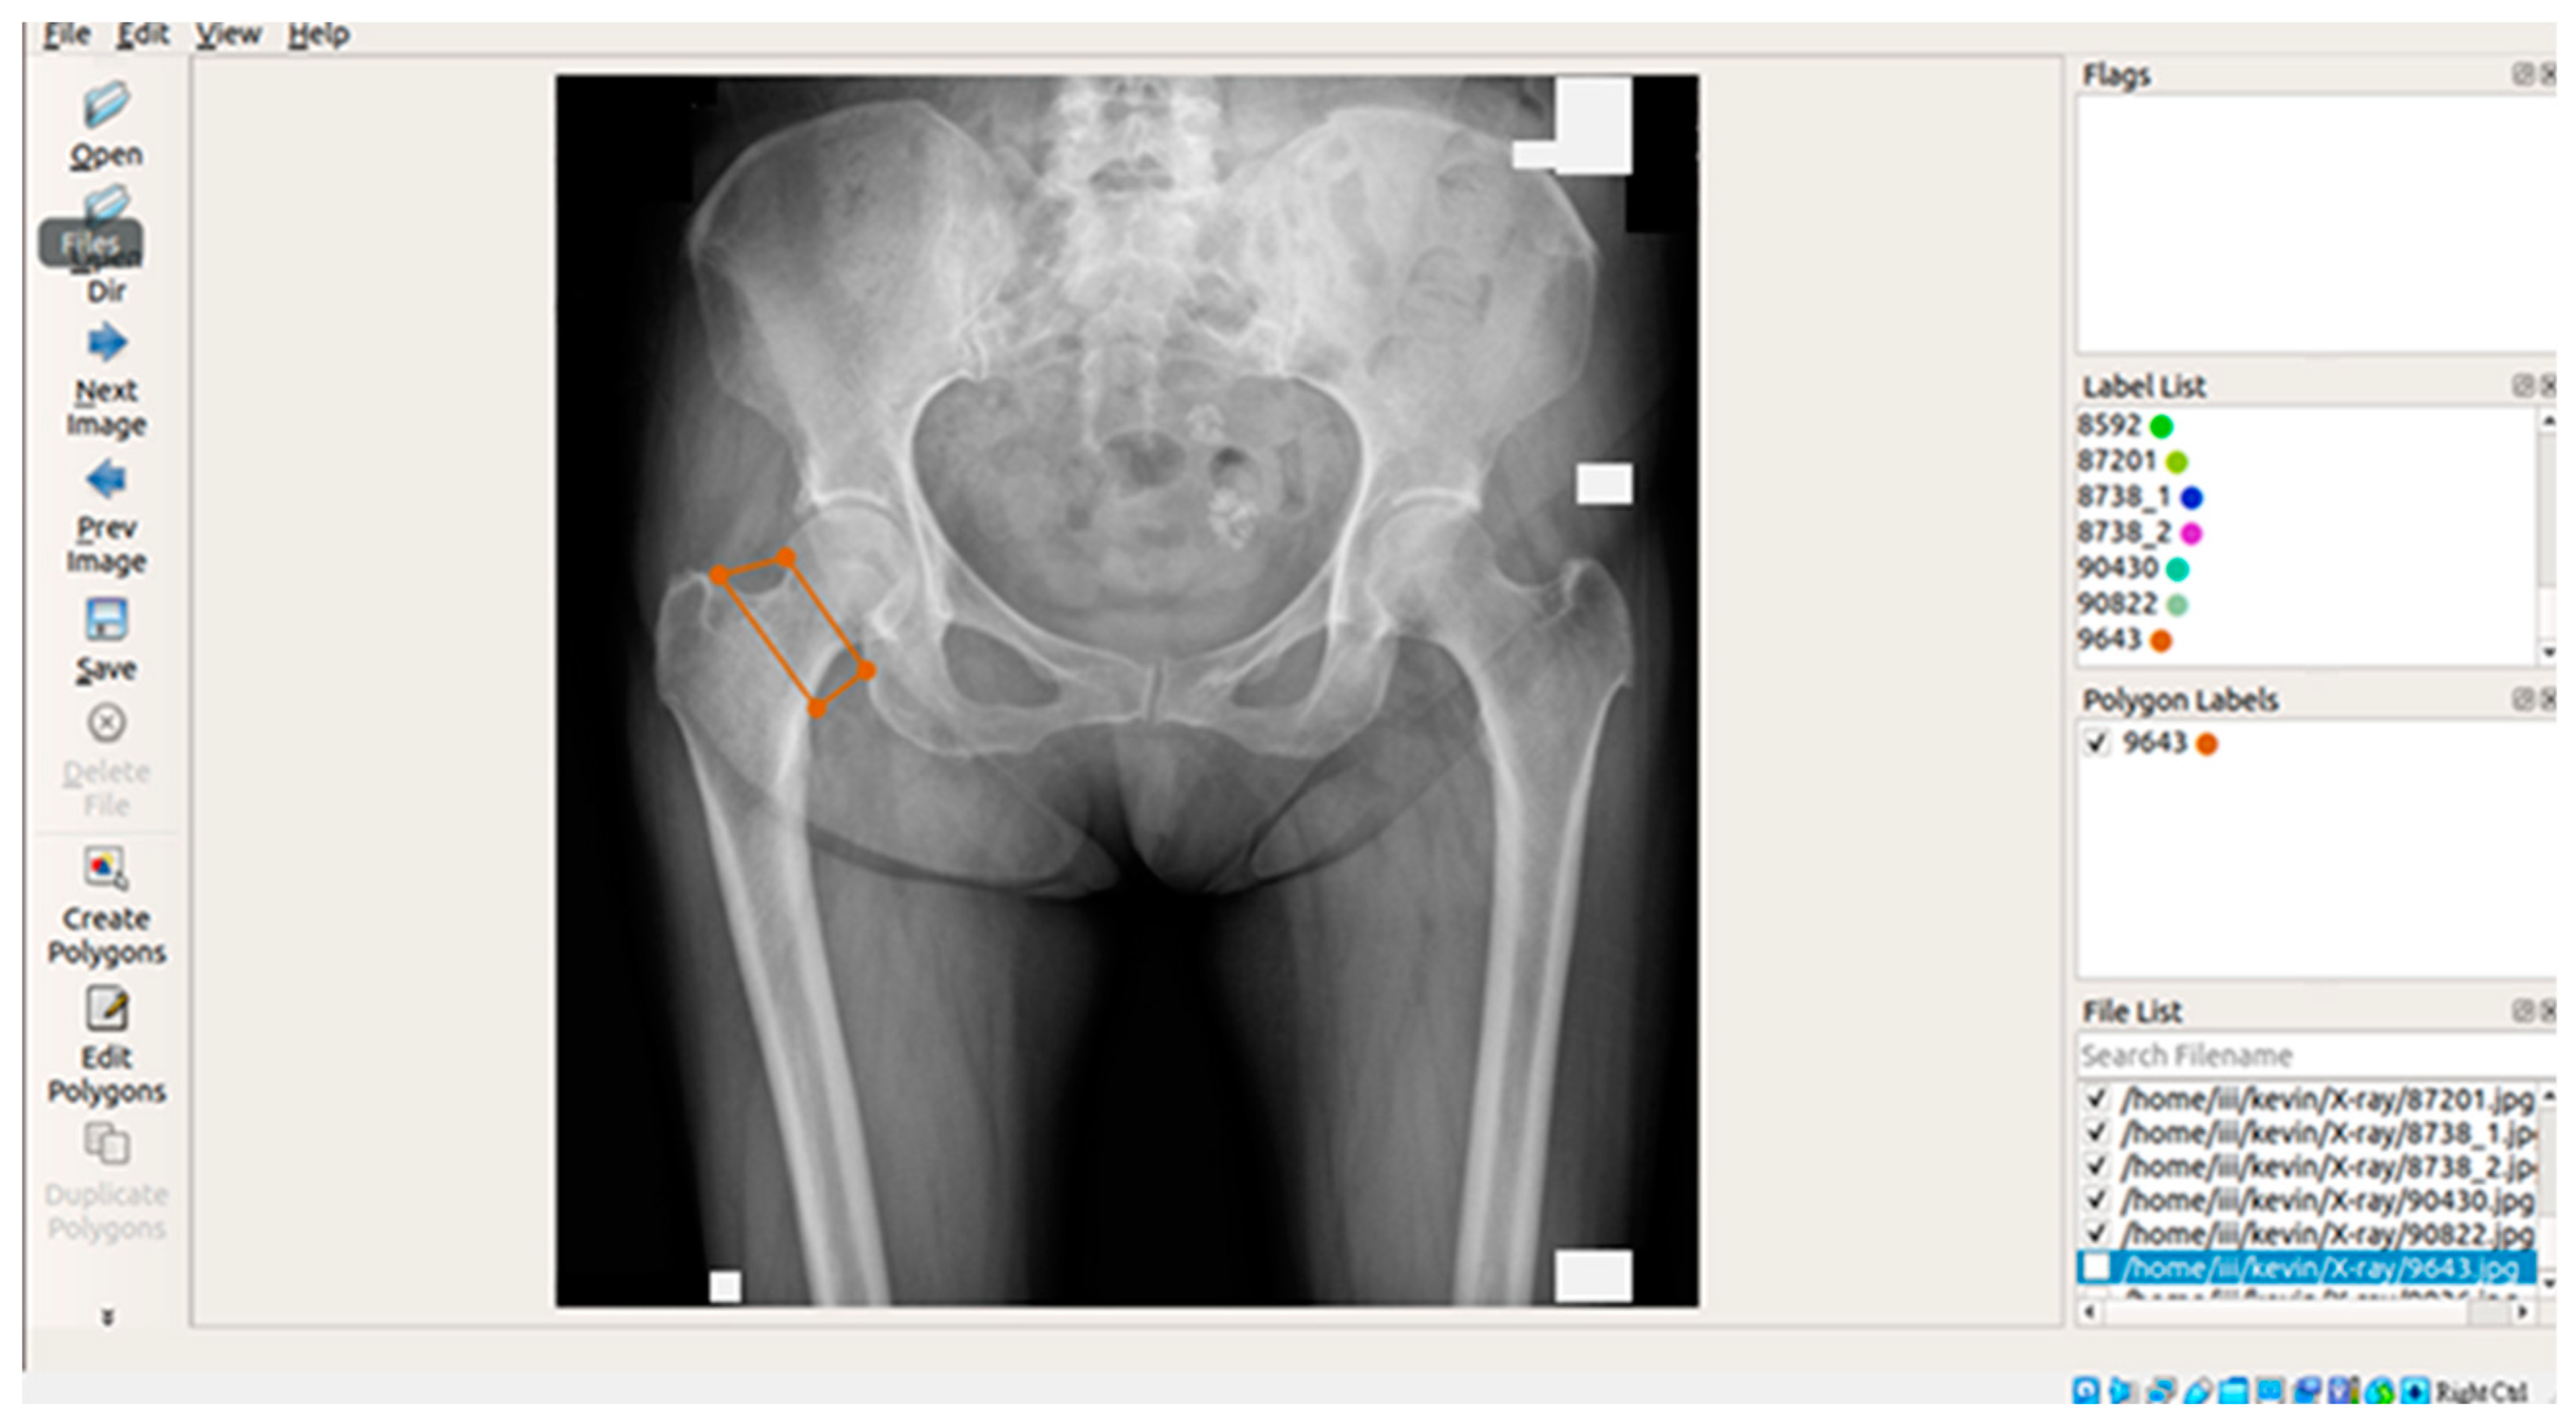

3.3.1. Image labeling

In this study, X-ray images of each of the four areas of the patient's hip (femoral neck, greater trochanter, wards triangle, and total hip) were separated and manually labeled using Labelme, an open-source tool that can be used for labeling [29]. The four parts of the hip were then framed as shown in Figure 2 below, and the labeled image data were batch converted into binary .png files, which were used as inputs for the supervised learning training of U-Net, U-Net++, and image categorization in the image segmentation process.